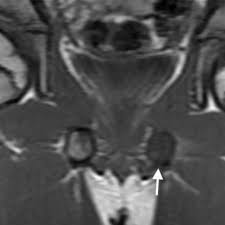

The different characteristics by images from simple radiography computed tomography MRI and bone. Van Neck-Odelberg disease is a benign process that develops in children between the ages of 4 and 16 years. Van Neck-Odelberg disease or ischiopubic osteochondritis is a rare cause of pain in the pediatric pelvis due to late closure in synchondrosis ischiopubic whose main symptom is an asymmetric pain that can cause a limitation in movement or limp.

It is a temporary joint which is slimming to obliterate a bone fusion with skeletal maturation. Se observa un engrosamiento con edema óseo a nivel de la sincondrosis isquiopubiana derecha adyacente al músculo obturador externo flecha. The van Neck-Odelberg disease is hyperostosis of ischiopubic synchondrosis IPS.

Se conoce entonces como síndrome de Van Neck-Odelberg a la osteocondritis isquiopúbica que se desarrolla en niños entre los 4 y 16 años. The literature to date contains fewer. A Case of van Neck-Odelberg Disease and Intermittent Overuse Injury Abstract. Van Neck-Odelberg disease is a benign process that develops in children between the ages of 4 and 16 years. Patients typically complain of vague groin or buttock pain. The different characteristics by images from simple radiography computed tomography MRI and bone. It is a temporary joint which is slimming to obliterate a bone fusion with skeletal maturation. Left leg dominant patient presented with pain in groin and limping with left leg dominance. Differential diagnosis such as stress fractures osteomyelitis tuberculosis post-traumatic osteolysis or any neoplasia is need be ruled out to arrive at diagnosis.

The synchondrosis ischiopubic SIP is the cartilaginous union between the lower ischium and pubis branch in infancy. BACKGROUND Van Neck disease VND is a benign skeletal abnormality of children involving a hyperostosis of the ischiopubic synchondrosis IPS seen on radiographs. Van Neck-Odelberg disease is a syndrome characterized by an atypical ossification pattern of the ischiopubic synchondrosis. The van Neck-Odelberg disease is hyperostosis of ischiopubic synchondrosis IPS. Der Morbus van Neck oder Morbus Odelberg-van Neck ist eine seltene Form der aseptische Knochennekrose im Bereich des Beckens Synchondrosis oder Osteochondrosis ischiopubica. In van Neck-Odelberg disease an enlarged anatomical structure called ischiopubic synchondrosis is susceptible. However the radiological findings corresponded instead to van NeckOdelberg diseasea rare benign aseptic bony necrosis of the ischiopubic.